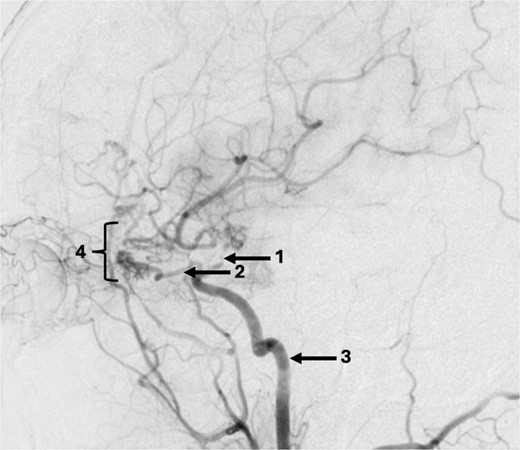

A 43-year-old lady, with known hypertension, presented with severe and sudden onset headache in 2010. Initial computed tomography (CT) head confirmed a diffuse subarachnoid haemorrhage (images not available) and a subsequent CT angiogram showed a right supraclinoid internal carotid artery (ICA) aneurysm (Fig. 1). CT Angiogram also showed an unruptured left posterior communicating which was thought not to be related to this patient’s presentation and managed conservatively with serial imaging. The patient underwent emergency craniotomy on the same day where an encircling Sundt clip was applied to secure the aneurysm. She made a full neurological recovery and was discharged from hospital. Post-operative day 1 CT angiogram demonstrated relatively normal calibre of the right A1 portion of anterior cerebral artery (ACA) and M1 portion of middle cerebral artery (MCA), in the terminal carotid region (Fig. 2).

Axial post-operative CT angiogram demonstrating the (1) encircling clip occlusion of the terminal internal carotid artery aneurysm with a relatively normal calibre of (2) A1 and, (3) M1.